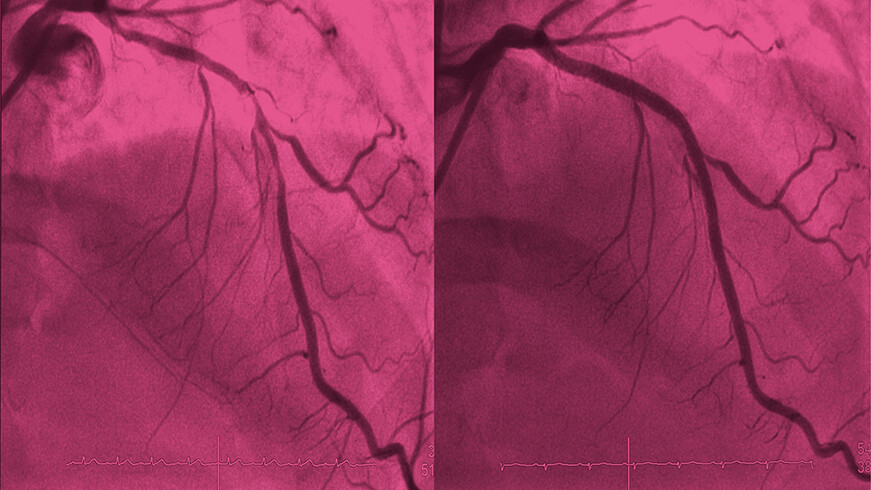

Perkutanen Koronarintervention (PCI) vor und nach der Behandlung Perkutanen Koronarintervention (PCI) vor und nach der Behandlung